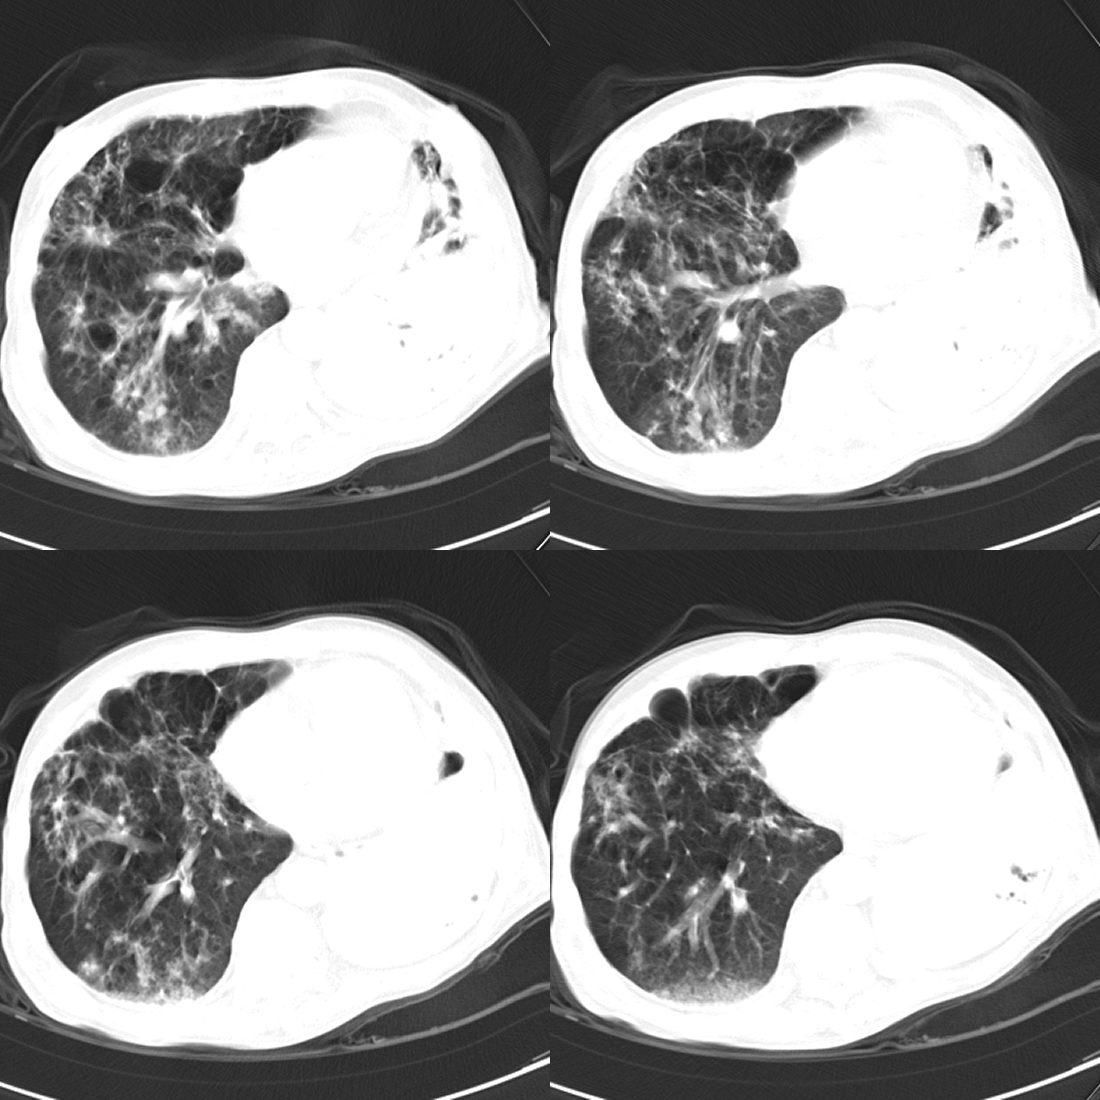

以下是引用zsl6918在2008-11-29 21:51:00的发言:[br]建议追问病史有无粉尘接触史,鉴别是结核还是矽肺。另外,左侧肺门的改变需强化明确,除外占位。

以下是引用liuyue在2008-11-30 6:01:00的发言:[br]双肺继发性肺结核;左侧包裹性积液;建议增强化或支气管镜检查除外左肺占位性病变.